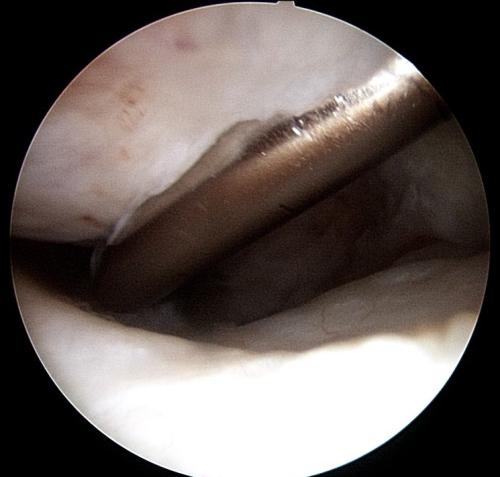

A rehabilitation program will be provided for your horse. This may also include suggestions for post-surgical treatments. For example, it is routine to perform Hyaluronic acid/corticosteroid injections at 2 weeks post surgery following arthroscopic chip/fragment removal. When there is substantial soft-tissue or cartilage injury, we often recommend biologic therapies.